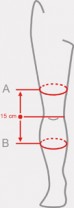

| Size | (A) Thigh circumference 15 cm above the center of the patella | (B) Calf circumference 15 cm below the center of the patella | How to measure |

| S | 40 – 44 cm 15,7″ – 17,3″ |

30 – 34 cm 11,8″ – 13,4″ |

|

| M | 44 – 48 cm 17,3″ – 18,9″ |

34 – 38 cm 13,4″ – 15″ |

|

| L | 48 – 52 cm 17,3″ – 20,1″ |

38 – 42 cm 15″ – 16,5″ |

|

| XL | 52 – 56 cm 20,5″ – 22″ |

42 – 46 cm 16,5″ – 18,1″ |

Right and left leg specific.